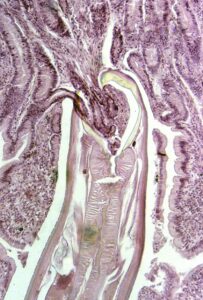

Scienziati australiani stanno sviluppando una nuova terapia contro i disturbi autoimmuni come la celiachia, un'intolleranza permanente al glutine presente nei...